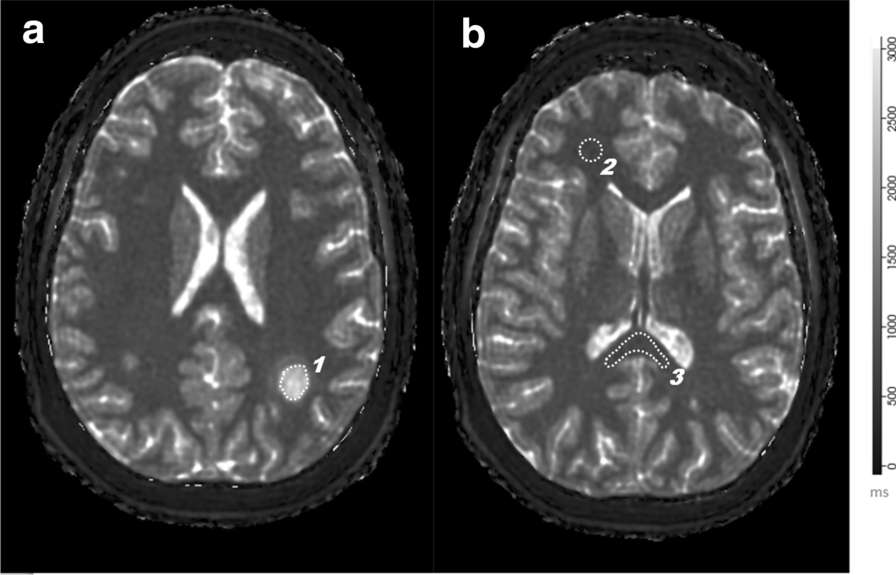

Region of Interest segmentations within MRF maps: MRF T1 relaxometry map demonstrating an active lesion in a patient with multiple sclerosis. a Depicts the lesion [1] in the parietal white matter and the corresponding ROI. The T1 and T2 values and the first order statistics were simultaneously obtained from this ROI. b shows the ROI over the frontal normal appearing white matter [2] and splenium [3]